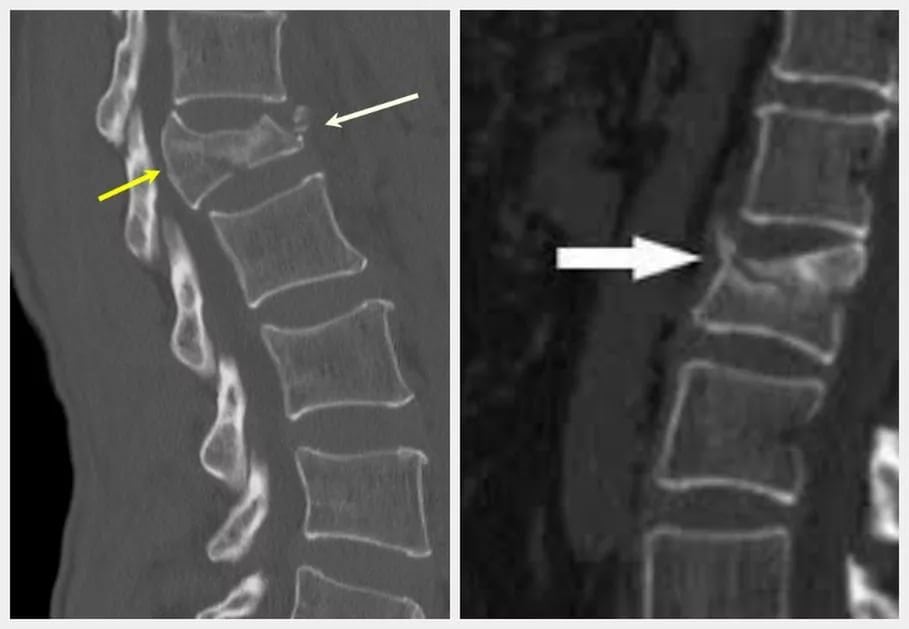

Оперативное вмешательство необходимо пациентам с остеопоротическими переломами позвоночника.

Большинство врачей для борьбы с ними использует вертебропластику и транспедикулярную фиксацию. При выполнении последней хирурги нередко сталкиваются с рядом трудностей. Основная из них – выраженное снижение плотности костной ткани. Иногда медикам приходится отказываться от транспедикулярной фиксации из-за высокого риска прорезывания винтов.

Заднюю стабилизацию позвоночника выполняют при свежих оскольчатых переломах одного или двух сегментов. Операции с передним доступом делают при застарелых переломах, переломовывихах, значительном снижении высоты тел позвонков и выраженной нестабильности позвоночника. Их также выполняют в случае неэффективности транспедикулярной фиксации. При полисегментарных переломах в поздней стадии больным показано введение цемента в тела позвонков.